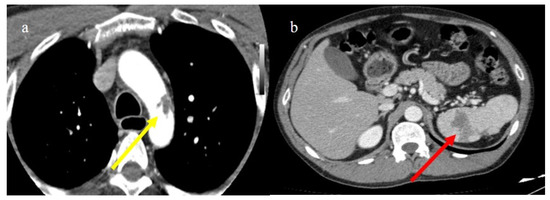

- Bonaffini, P.A.; Franco, P.N.; Bonanomi, A.; Giaccherini, C.; Valle, C.; Marra, P.; Norsa, L.; Marchetti, M.; Falanga, A.; Sironi, S. Ischemic and hemorrhagic abdominal complications in COVID-19 patients: Experience from the first Italian wave. Eur. J. Med. Res. 2022, 27, 1–9. [Google Scholar] [CrossRef]

- Evrev, D.; Sekulovski, M.; Gulinac, M.; Dobrev, H.; Velikova, T.; Hadjidekov, G. Retroperitoneal and abdominal bleeding in anticoagulated COVID-19 hospitalized patients: Case series and brief literature abdominal bleeding in anticoagulated COVID-19 hospitalized patients: Case series and brief literature review. World J. Clin. Cases 2023, 11, 1528–1548. [Google Scholar] [CrossRef] [PubMed]

- Sposato, B.; Croci, L.; Di Tomassi, M.; Puttini, C.; Olivieri, C.; Alessandri, M.; Ronchi, M.C.; Donati, E.; Garcea, A.; Brazzi, A.; et al. Spontaneous abdominal bleeding associated with SARS-CoV-2 infection: Causality or coincidence? Acta Biomed. 2021, 92, e2021199. [Google Scholar] [PubMed]

- Mahboubi-Fooladi, Z.; Arabi, K.P.; Khazaei, M.; Nekooghadam, S.; Shadbakht, B.; Moharamzad, Y.; Taheri, M.S. Parenteral Anticoagulation and Retroperitoneal Hemorrhage in COVID-19: Case Report of Five Patients. SN ComPract. Clin. Med. 2021, 3, 2005–2010. [Google Scholar] [CrossRef] [PubMed]

- Dubovský, M.; Hajská, M.; Panyko, A.; Vician, M. Severe Retroperitoneal Hemorrhage in a COVID-19 Patient on a Therapeutic Dose of Low Molecular Weight Heparin: A Case Report. Cureus 2022, 14, 26275. [Google Scholar] [CrossRef] [PubMed]

- Yeoh, W.C.; Lee, K.T.; Zainul, N.H.; Alwi, S.B.S.; Low, L.L. Spontaneous retroperitoneal hematoma: A rare bleeding occurrence in COVID-19. Oxf. Med. Case Rep. 2021, 2021, omab081. [Google Scholar] [CrossRef] [PubMed]

- Shah, M.; Colombo, J.P.; Chandna, S.; Rana, H. Life-Threatening Retroperitoneal Hematoma in a Patient with COVID-19. Case Rep. Hematol. 2021, 2021, e8774010. [Google Scholar] [CrossRef]

- Belfiore, M.P.; Russo, G.M.; Gallo, L.; Atripaldi, U.; Tamburrini, S.; Caliendo, V.; Impieri, L.; Del Canto, M.T.; Ciani, G.; Parrella, P.; et al. Secondary Complications in COVID-19 Patients: A Case Series. Tomography 2022, 8, 1836–1850. [Google Scholar] [CrossRef]